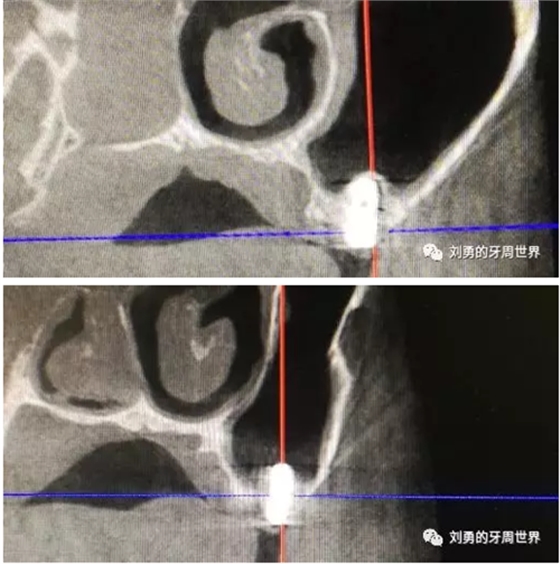

在手術(shù)之前行ct檢查如下圖:

可見(jiàn)B5種植體已經(jīng)脫落進(jìn)入上頜竇,而上頜竇黏膜已經(jīng)出現(xiàn)明顯的炎癥,上頜竇黏膜明顯增厚,(在二期切開(kāi)手術(shù)之前上頜竇黏膜厚度正常)。而在ct上可以看到左側(cè)上頜竇中鼻道開(kāi)口不通暢。